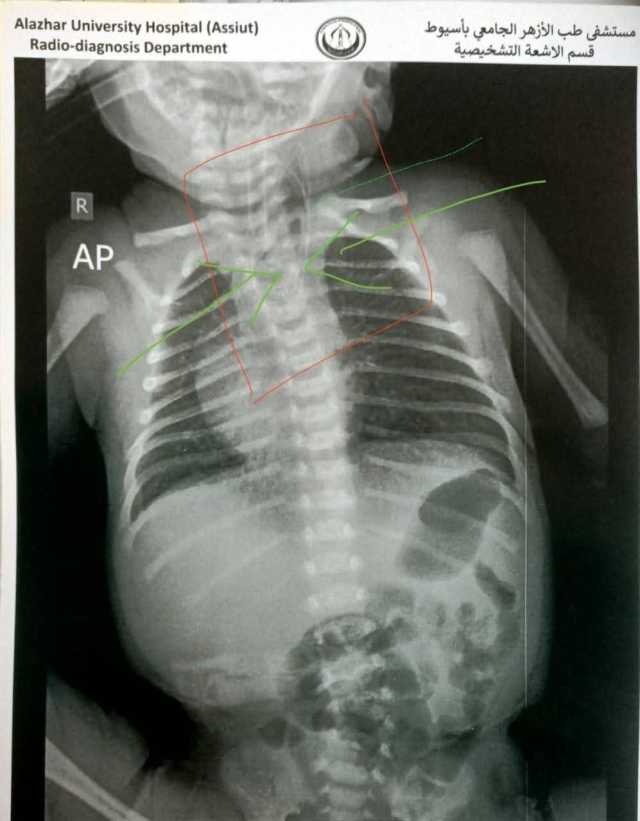

جراحة دقيقة 4 ساعات.. فريق طبي بمستشفى جامعة الأزهر بأسيوط ينقذ حياة رضيع

نجح فريق طبي بمستشفى جامعة الأزهر بأسيوط في إنقاذ حياة رضيع عمره 7 أيام، بعد إجراء جراحة معقدة استغرقت  4 ساعات، لعلاج حالة نادرة من انسداد بالمريء مصحوب بناسور كبير يصل إلى القصبة الهوائية، وهو ما تسبب في صعوبة شديدة في التنفس وعدم القدرة على الرضاعة منذ ولادته.

انسداد كامل بالمريء

وأوضح عميد كلية الطب ورئيس مجلس إدارة مستشفى الأزهر الجامعي بأسيوط أن نتائج الفحوصات أكدت وجود انسداد كامل بالمريء وناسور بحجم كبير بين المريء والقصبة الهوائية، مما استدعى التدخل الفوري لإنقاذ حياة الطفل. وتم تجهيز غرفة العمليات لإجراء الجراحة التي تُعد من أعقد جراحات الأطفال، وتتطلب دقة ومهارة عالية.

وأكد عميد كلية الطب أن الفريق الطبي تمكّن، خلال 4 ساعات من العمل فصل الناسور تمامًا عن القصبة الهوائية، وإعادة توصيل المريء بنجاح، إلى جانب تركيب قسطرة وريدية مركزية لضمان استمرار تقديم العلاج اللازم للرضيع عقب الجراحة. وخرج الطفل من غرفة العمليات في حالة مستقرة.